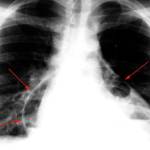

Из инструментальных методов в диагностике пневмомедиастинума используются:

- рентгенографическое исследование органов грудной клетки – на снимках выявляют полосы газа, средостение может быть «сжато» в размерах;